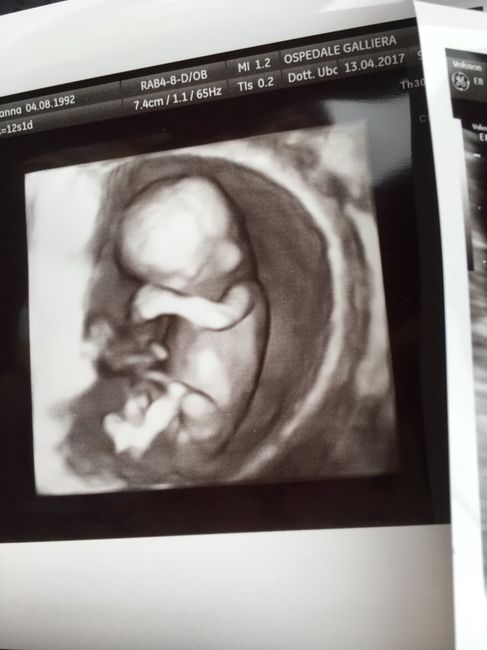

Secondo il ginecologo è una femminuccia

È stata per me L ecografie più emozionante di tutte, vederlo tutto formato e saltare da una parte all altra è qualcosa di indescrivibile, vi allego le fotine